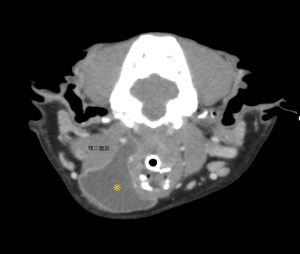

唾液は、唾液腺(下顎腺、舌下腺、頬骨腺、耳下腺)で作られ、導管を通って口の中に流れる消化液です。唾液瘤は、なんらかの原因による導管の損傷により唾液が周囲に漏出する疾患です。通常は無症状ですが、部位によっては気道を圧迫したり、飲み込みづらくなったり、感染から敗血症になる事もあります。

今回のワンちゃんは、CT検査で舌下腺との連続性が確認できたため、下顎腺と舌下腺と導管を切除しました。導管は顎舌骨筋を切開したり、舌神経をくぐらせたり、可能な限り先端まで切除しました。できるだけ先端まで切除することで、再発を防ぐ事ができます。